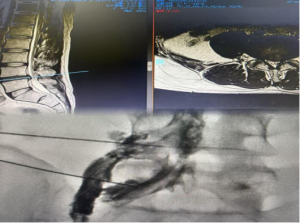

患者为31岁男性,因“腰椎间盘突出伴神经根病”收入医院脊柱外科。影像学检查明确提示腰4/5椎间盘左后方突出,压迫神经根,导致剧烈腰腿疼痛,严重影响生活质量。因为患者既往有白血病病史,处于造血干细胞移植后状态,白细胞长期低于正常水平,机体免疫防御能力极度脆弱。若实施常规的椎间孔镜等有创手术,围手术期感染风险极高。

2025年12月15日,在完善的术前准备和精确的影像引导下,疼痛诊疗科团队顺利为患者实施上述联合手术。手术过程顺利,患者耐受良好。术后,患者之前难以忍受的腰腿痛症状得到明显减轻。经过短期观察与康复,患者疼痛控制满意后出院。

术前腰椎MRI及术中图片